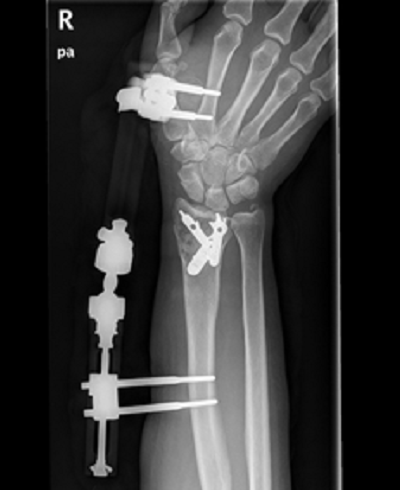

病例一:

诊断:桡骨极远端骨折。

治疗:内固定加外固定治疗。